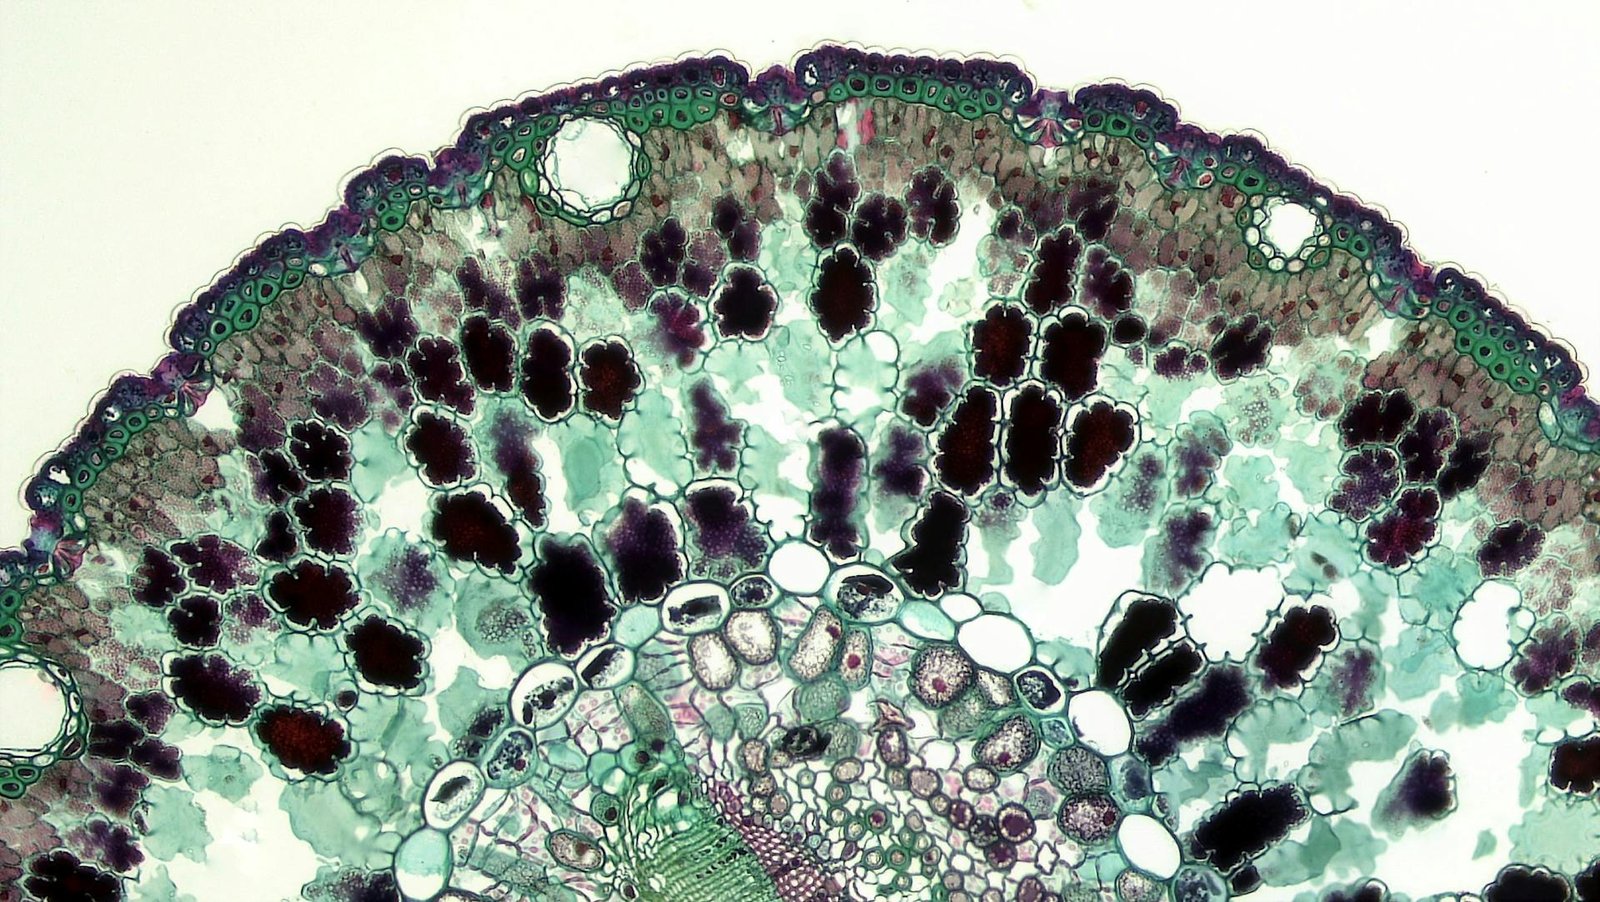

Mesenchymal stem cells (MSCs) are a type of multipotent adult stem cell first discovered in bone marrow but also present in adipose tissue, umbilical cord, placenta, dental pulp, and other sources.

- MSCs can self-renew and differentiate into osteoblasts (bone cells), chondrocytes (cartilage cells), and adipocytes (fat cells).

- They express specific surface markers (positive for CD73, CD90, CD105; negative for CD34, CD45).

- They can be expanded in culture and retain therapeutic properties. In simple language, it means that we can extract few MSC cells from certain tissues like fat cells (most readily accessible source in patients), and then multiply them in labs to increase their quantity to manage health conditions.

- Easy to isolate and expand in vitro

- Low immunogenicity (can be used allogeneically)

- Potent anti-inflammatory and regenerative properties